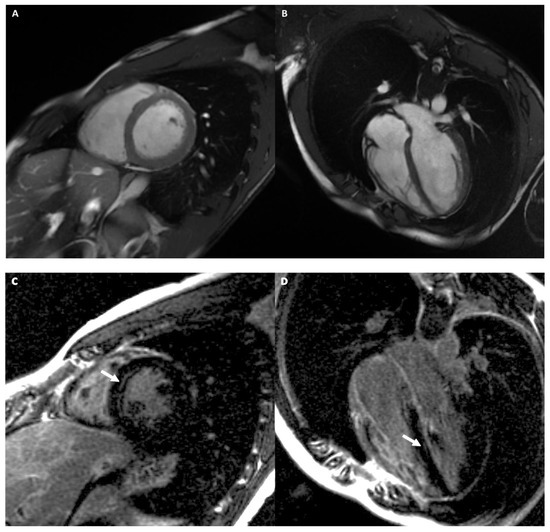

Arrhythmogenic Right Ventricular Cardiomyopathy

Left Dominant Arrhythmogenic Cardiomyopathy (LDAC)

- Palumbo, P.; Cannizzaro, E.; Di Cesare, A.; Bruno, F.; Schicchi, N.; Giovagnoni, A.; Splendiani, A.; Barile, A.; Masciocchi, C.; Di Cesare, E. Cardiac magnetic resonance in arrhythmogenic cardiomyopathies. Radiol. Med. 2020, 125, 1087–1101. [Google Scholar] [CrossRef]

- Miles, C.; Finocchiaro, G.; Papadakis, M.; Gray, B.; Westaby, J.; Ensam, B.; Basu, J.; Parry-Williams, G.; Papatheodorou, E.; Paterson, C.; et al. Sudden Death and Left Ventricular Involvement in Arrhythmogenic Cardiomyopathy. Circulation 2019, 139, 1786–1797. [Google Scholar] [CrossRef] [PubMed]